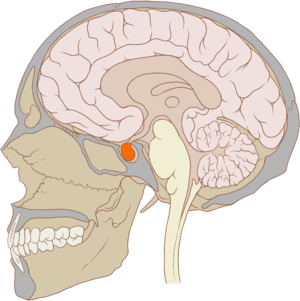

Location of the pituitary gland in the human brain

Pituitary and pineal glands